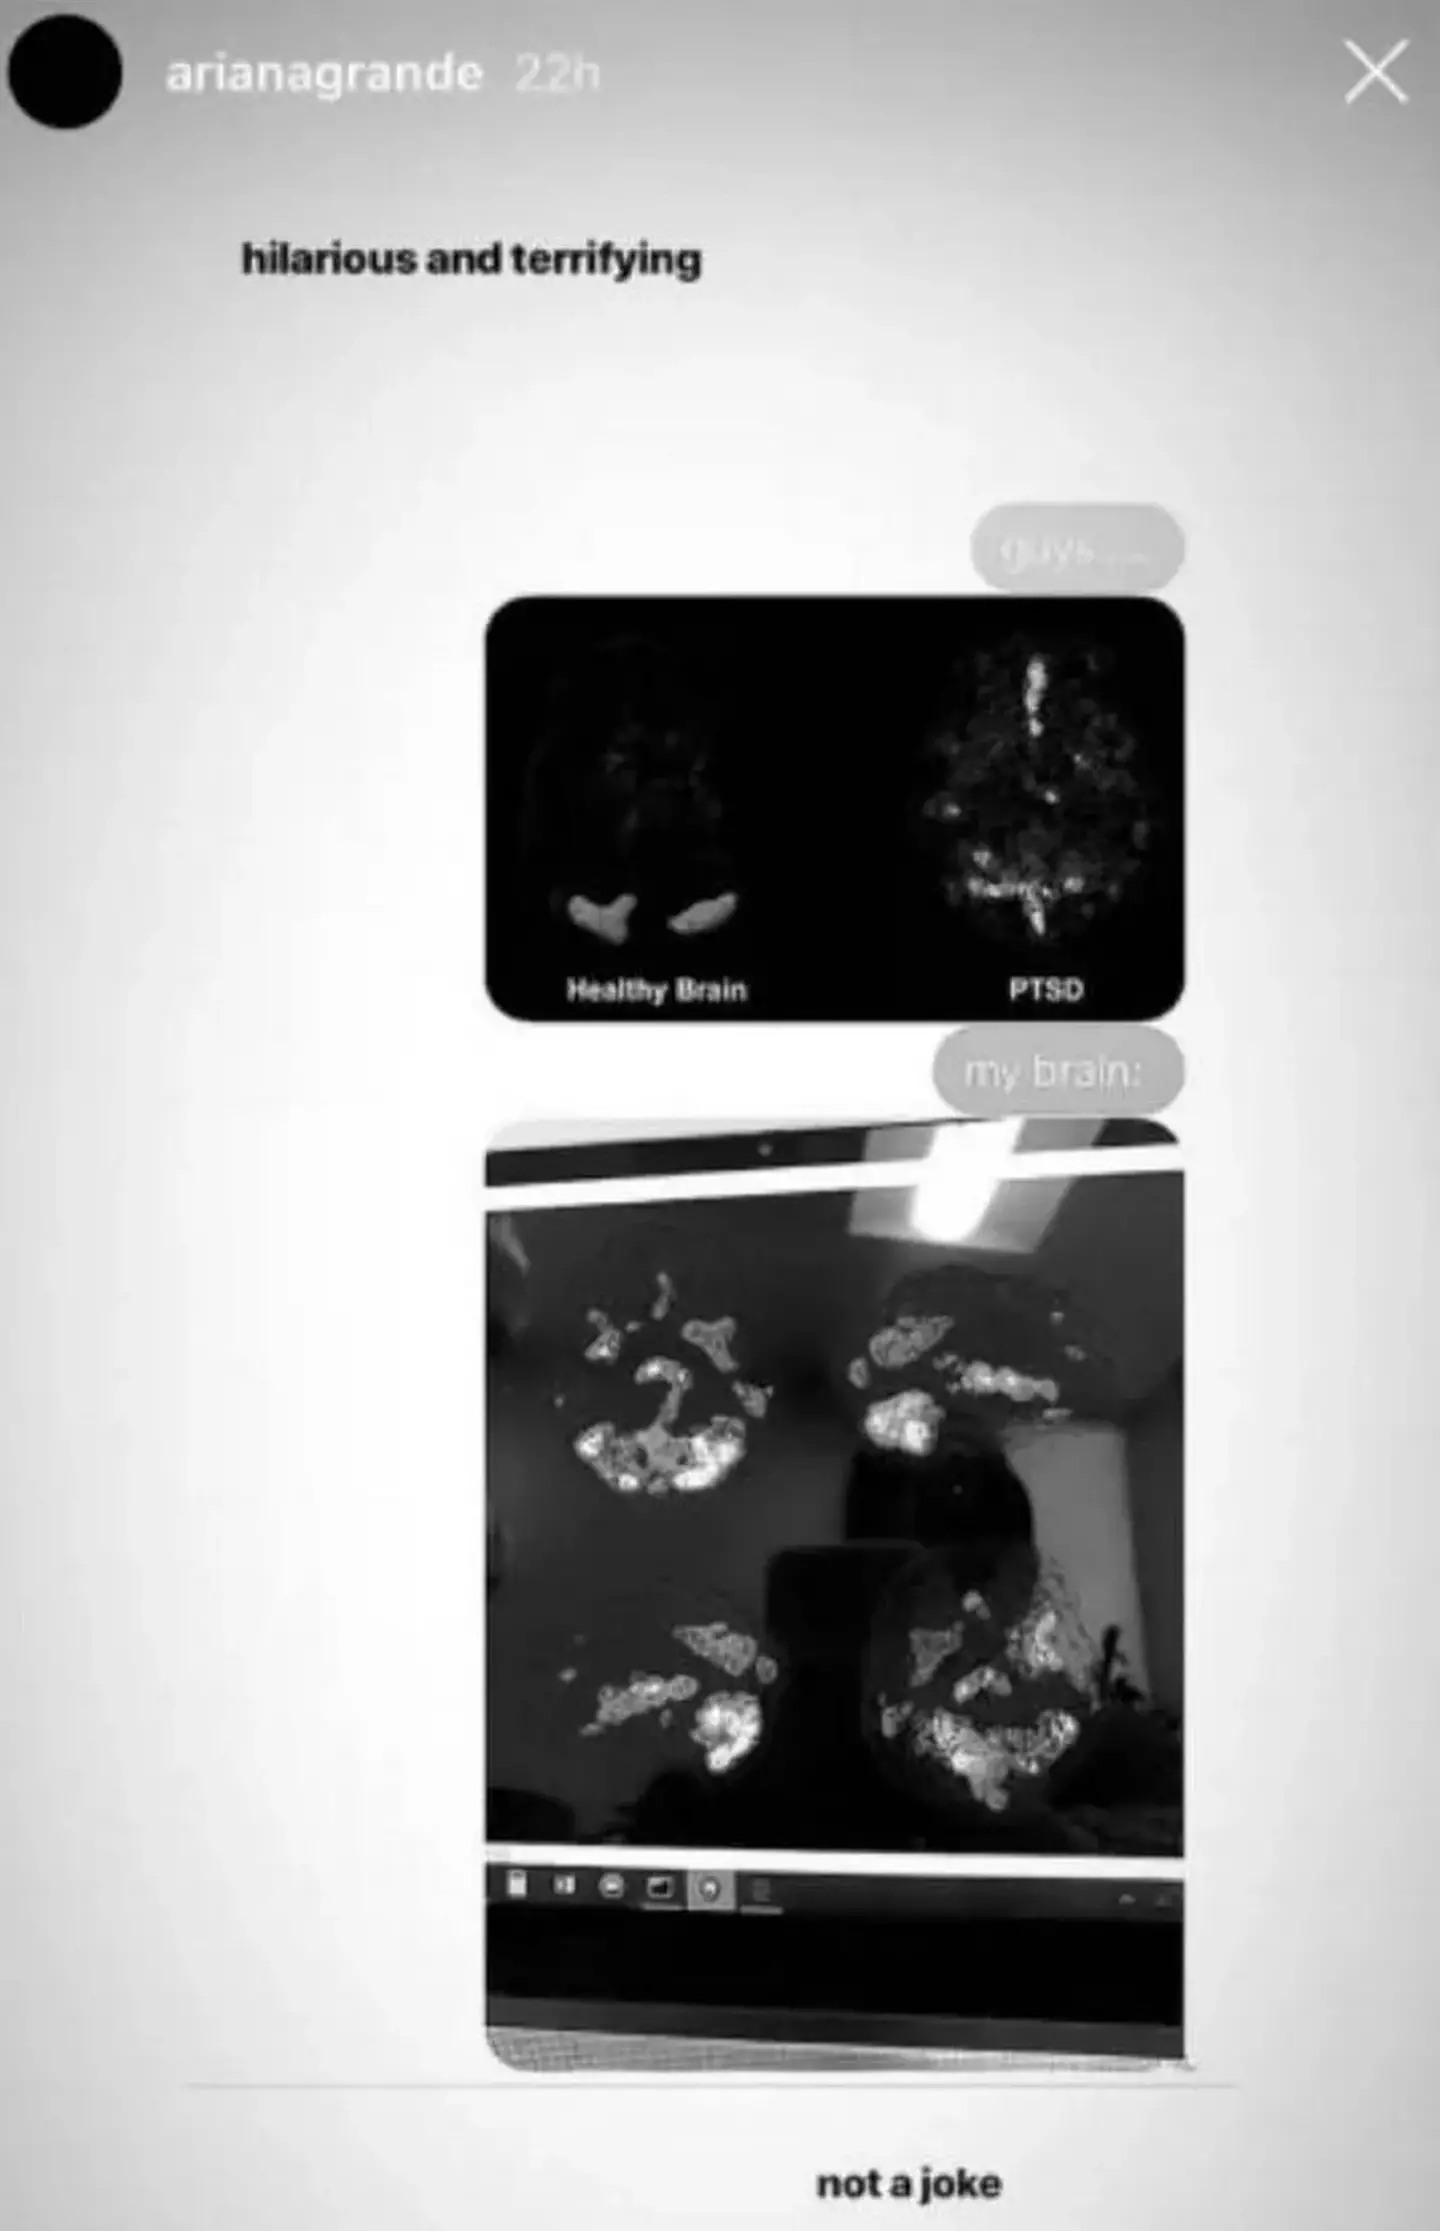

Back in 2019, Grande shared an image of her brain scan on her Instagram story which seriously shocked fans - despite her humorous caption stating the scans were 'hilarious and terrifying'.

Noting the post was 'not a joke', the images showed an image of a 'healthy brain' vs a brain of someone with PTSD which had a few small areas highlighted.

Accompanying the image was an image of her own brain scan, which had significantly more areas highlighted than the previous image that showed a brain with post-traumatic stress disorder (PTSD).